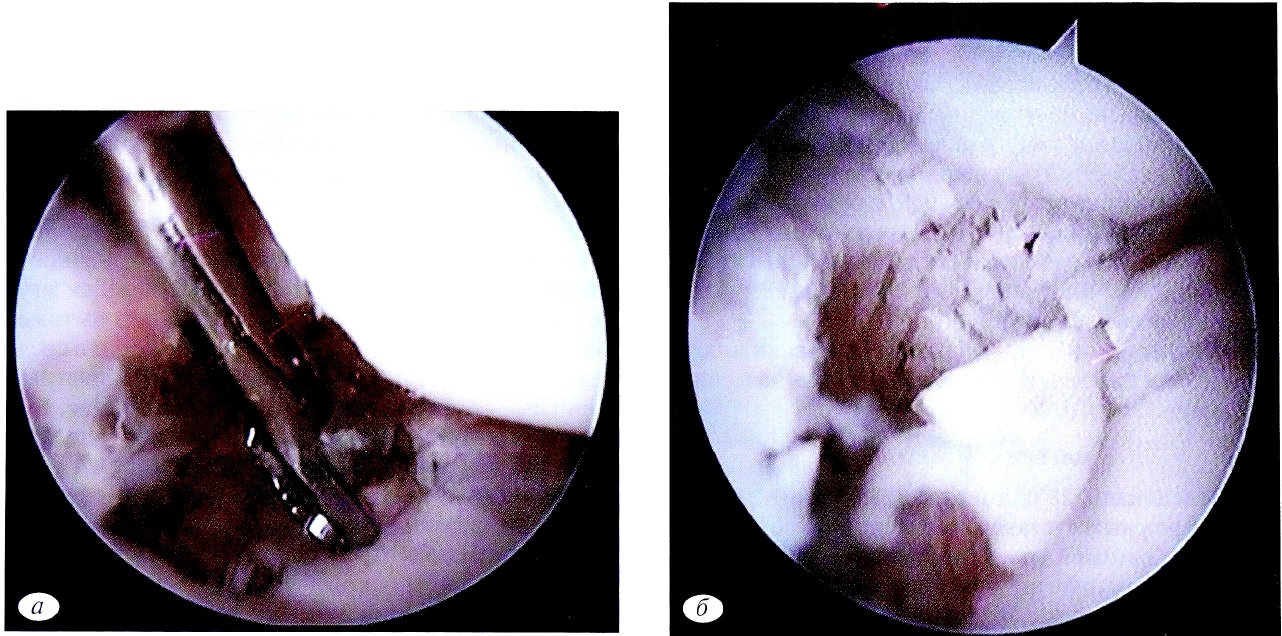

Далее под артроскопическим и рентгеновским контролем проводили 3 спицы: одна — осевая, проходящая сразу через дистальный и проксимальный отломки ладьевидной кости. Две другие спицы проходили только через дистальный отломок. Затем из крыла подвздошной кости брали губчатый костный трансплантат по типу «стружки», средний размер одного костного трансплантата — 0,2×0,2 см (рис. 4, а). Шахту заполняли костными трансплантатами (см. рис. 4, б) и вводили в зону ложного сустава (см. рис. 4, в) через ЛуСП.

Рис. 4. Обработка губчатого костного аутотрансплантата (а); заполнение шахты костной «стружкой» (б), введение костных трансплантатов в зону ложного сустава (в).

Fig. 4. Fragmentation spongy bone (a); bone graft filling (b); insertion of a bone graft into the pseudoarthrosis zone (c).

В среднем в зону ложного сустава вводили 3—5 порций костного трансплантата. После чего доводили две оставшиеся спицы в проксимальный отломок ладьевидной кости. Спицы скусывались подкожно.